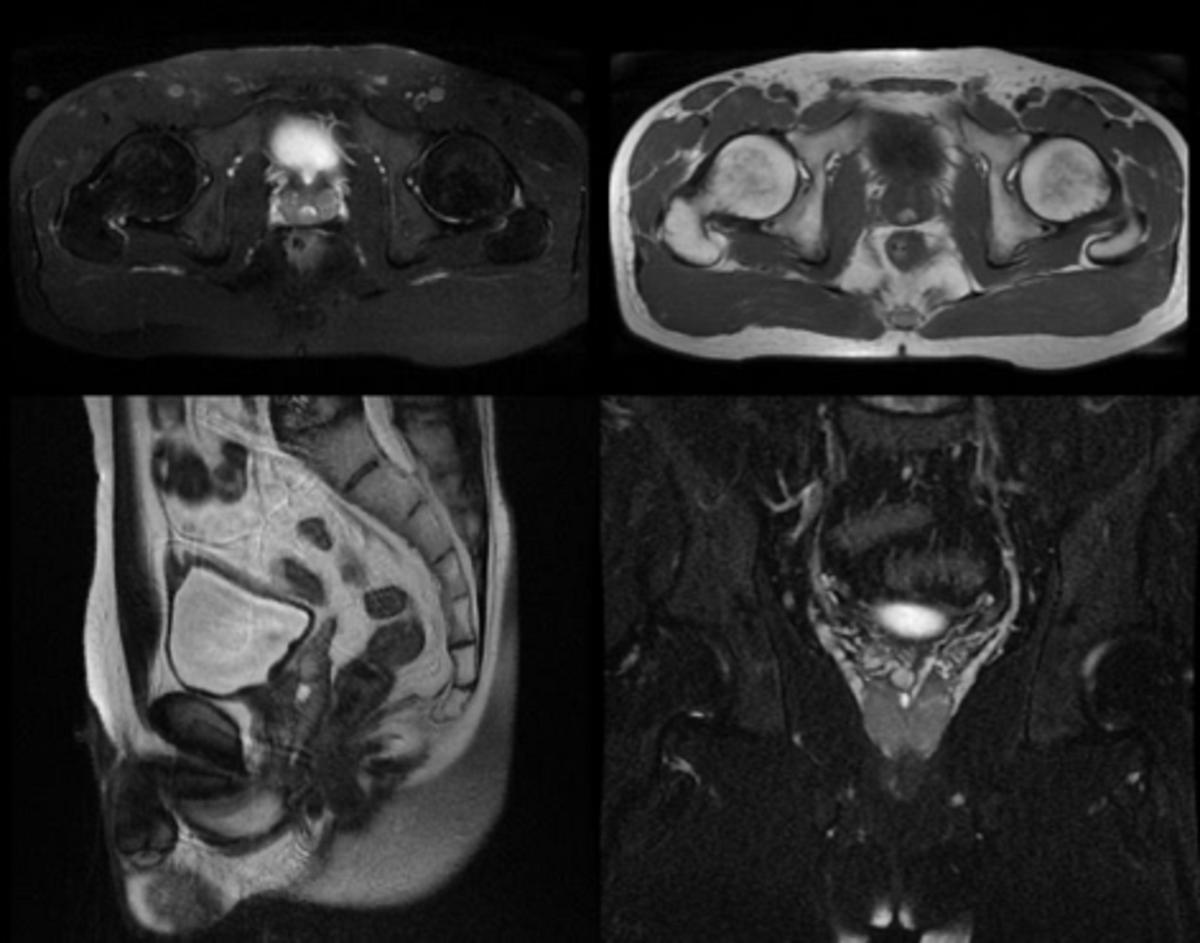

术前核磁共振检查提示:在前列腺后上方中线处有一类似“倒梨形”长T2信号影。